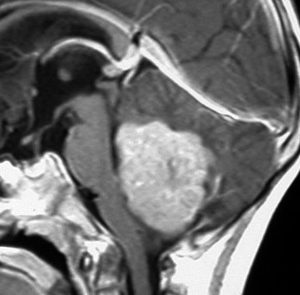

この例は,小脳半球にできたものです。のう胞(水たまり)を形成しています。髄芽腫の大きな特徴は,造影剤を入れないCT(左側)で腫瘍が少し白く見えることです(灰白質より高密度といいます)。細胞密度が高いので高密度になります。この例はclassic medulloblastomaですが,MIB-1は45%に達するもので,急激な腫瘍発育を示します。